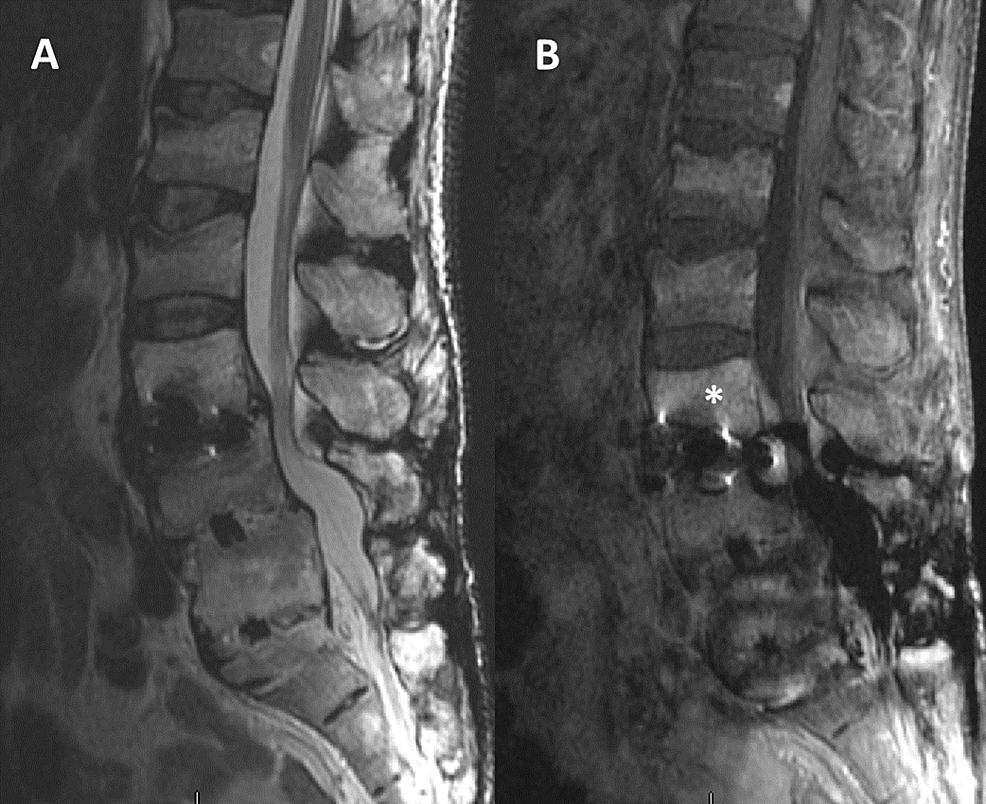

Spinal fusion is surgery to join two or more vertebrae into one single structure. Metal screws that stabilize the spine may move or break before the bones are. Spinal infections are rare, but, when they happen, they can be destructive if not treated promptly and properly.